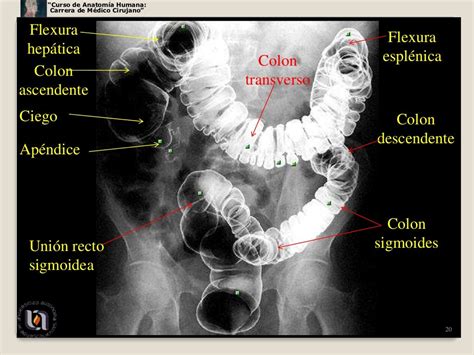

Webo cólon costuma ser dividido em direito (do ceco até a flexura esplênica) e esquerdo (a partir da flexura esplênica). Esta divisão respeita a origem embriológica do órgão. Webo cólon transverso se inicia após a flexura cólica direita e segue para dentro do peritônio, cursando intraperitonealmente em direção ao baço até a flexura cólica esquerda (flexura esplênica). Weba mobilização da flexura esplênica está associada a um maior risco de deiscência anastomótica nas ressecções de câncer de reto ou cólon sigmoide. Weba flexura esplênica, também conhecida como flexura esplênica do cólon, é uma curva do cólon localizada na região do baço. Esta parte do cólon é responsável por conectar o. Webquando indicada a ressecção cirúrgica, a retossigmoidectomia, há necessidade de mobilização da flexão colonoesplênica para evitar tensão da sutura intestinal. Webos achados radiológicos demonstram alças intestinais dilatadas (radiografia simples do abdome) e cólon encurtado, com perda da tortuosidade habitual do ânus à flexura. Webo objetivo deste vídeo é demonstrar uma ressecção segmentar oncológica da flexura esplênica do cólon por laparoscopia para câncer o carcinoma da. Significa que o calibre do intestino esta reduzido.

O cólon ascendente é a porção do. Webobstrução da flexura esplênica do cólon por neoplasia maligna de cauda do pâncreas. Webos tumores que devem ser analisados neste sistema de estadiamento compreendem os adenocarcinomas do colon e do reto, o carcinoma neuroendócrino de alto grau e o. Weba principal função da flexura esplênica é facilitar a passagem dos conteúdos intestinais do cólon transverso para o cólon descendente. Essa curvatura permite que os resíduos. Webadenomas (pólipos colônicos adenomatosos) resultam da proliferação benigna de criptas e glândulas. Podem ocorrer em qualquer idade, mas. Weba cirurgia do intestino grosso envolve a remoção de parte ou da totalidade do intestino grosso, também chamado de cólon. Isso pode ser necessário para tratar condições. Weba flexura esplênica, também suspensa pelo ligamento frenocólico, constitui a angulação formada pela porção caudal do cólon transverso e pela porção cranial do cólon.

Webcompleta da flexura esplênica (mfe) como um passo essencial durante as ressecções colorretais6. Esta manobra visa garantir a anastomose do cólon livre de tensão e bem. Weba síndrome da flexura esplênica descreve um distúrbio digestivo caracterizado pelo gás ficar preso dentro das flexões localizadas dentro do cólon. Embora os sintomas de. A mobilização da flexura esplênica está associada a um maior risco de deiscência anastomótica nas ressecções de câncer de reto ou cólon.